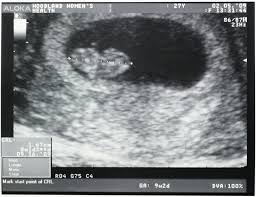

GS – Gestational sac diameter

Boleh dikira mulai 4W +4D. Meningkat 1cm setiap hari. Ukur GS dari hujung ke hujung. Ukur sehingga

tiga kali, dapatkan ukuran terbesar, bandingkan dengan POA pelanggan.

Lihat jika ada CRL. Dan jika ada

lihat degupan jantung fetal.